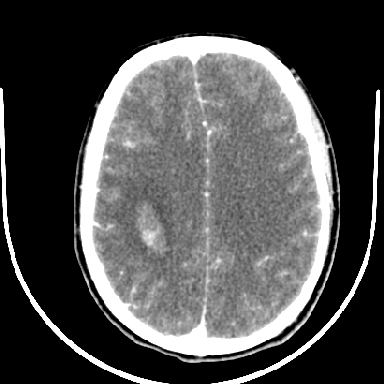

m 40突发头痛左侧偏瘫3小时

考虑高血压性脑出血,依据:

1是高血压性脑出血的好发部位,形态呈肾形,是高血压性脑出血的常见形状

3病灶周围水肿不是太厉害,一般肿瘤出血水肿多非常明显

4病灶周围的‘软组织’影没有明显的强化

5至于脑血管畸形引起的出血,暂时没有看到明显的畸形血管影,也不太支持

支持右侧基底节脑出血

右侧基底节区脑出血.

支持右侧基底节区(主要为外囊区)原发性脑出血。

支持右侧基底节区(主要为外囊区)原发性脑出血

支持右侧基底节区(主要为外囊区)原发性脑出血----有无血管畸形及动脉瘤或说出血原因待查

另附部分资料:“血液溢出血管外形成血肿,其内含有大量血红蛋白、血浆白蛋白,球蛋白,因这些蛋白对x线的吸收系数高于脑质,故ct呈现高密度阴影,ct值达40~90h,最初高密度灶呈非均匀一致性,中心密度更高,新鲜出血灶边缘不清。基底节区血肿多为“肾”型,内侧凹陷,外侧膨隆,因外侧裂阻力较小,故向外凸,其它部位血肿多呈尖圆形或不规则形”